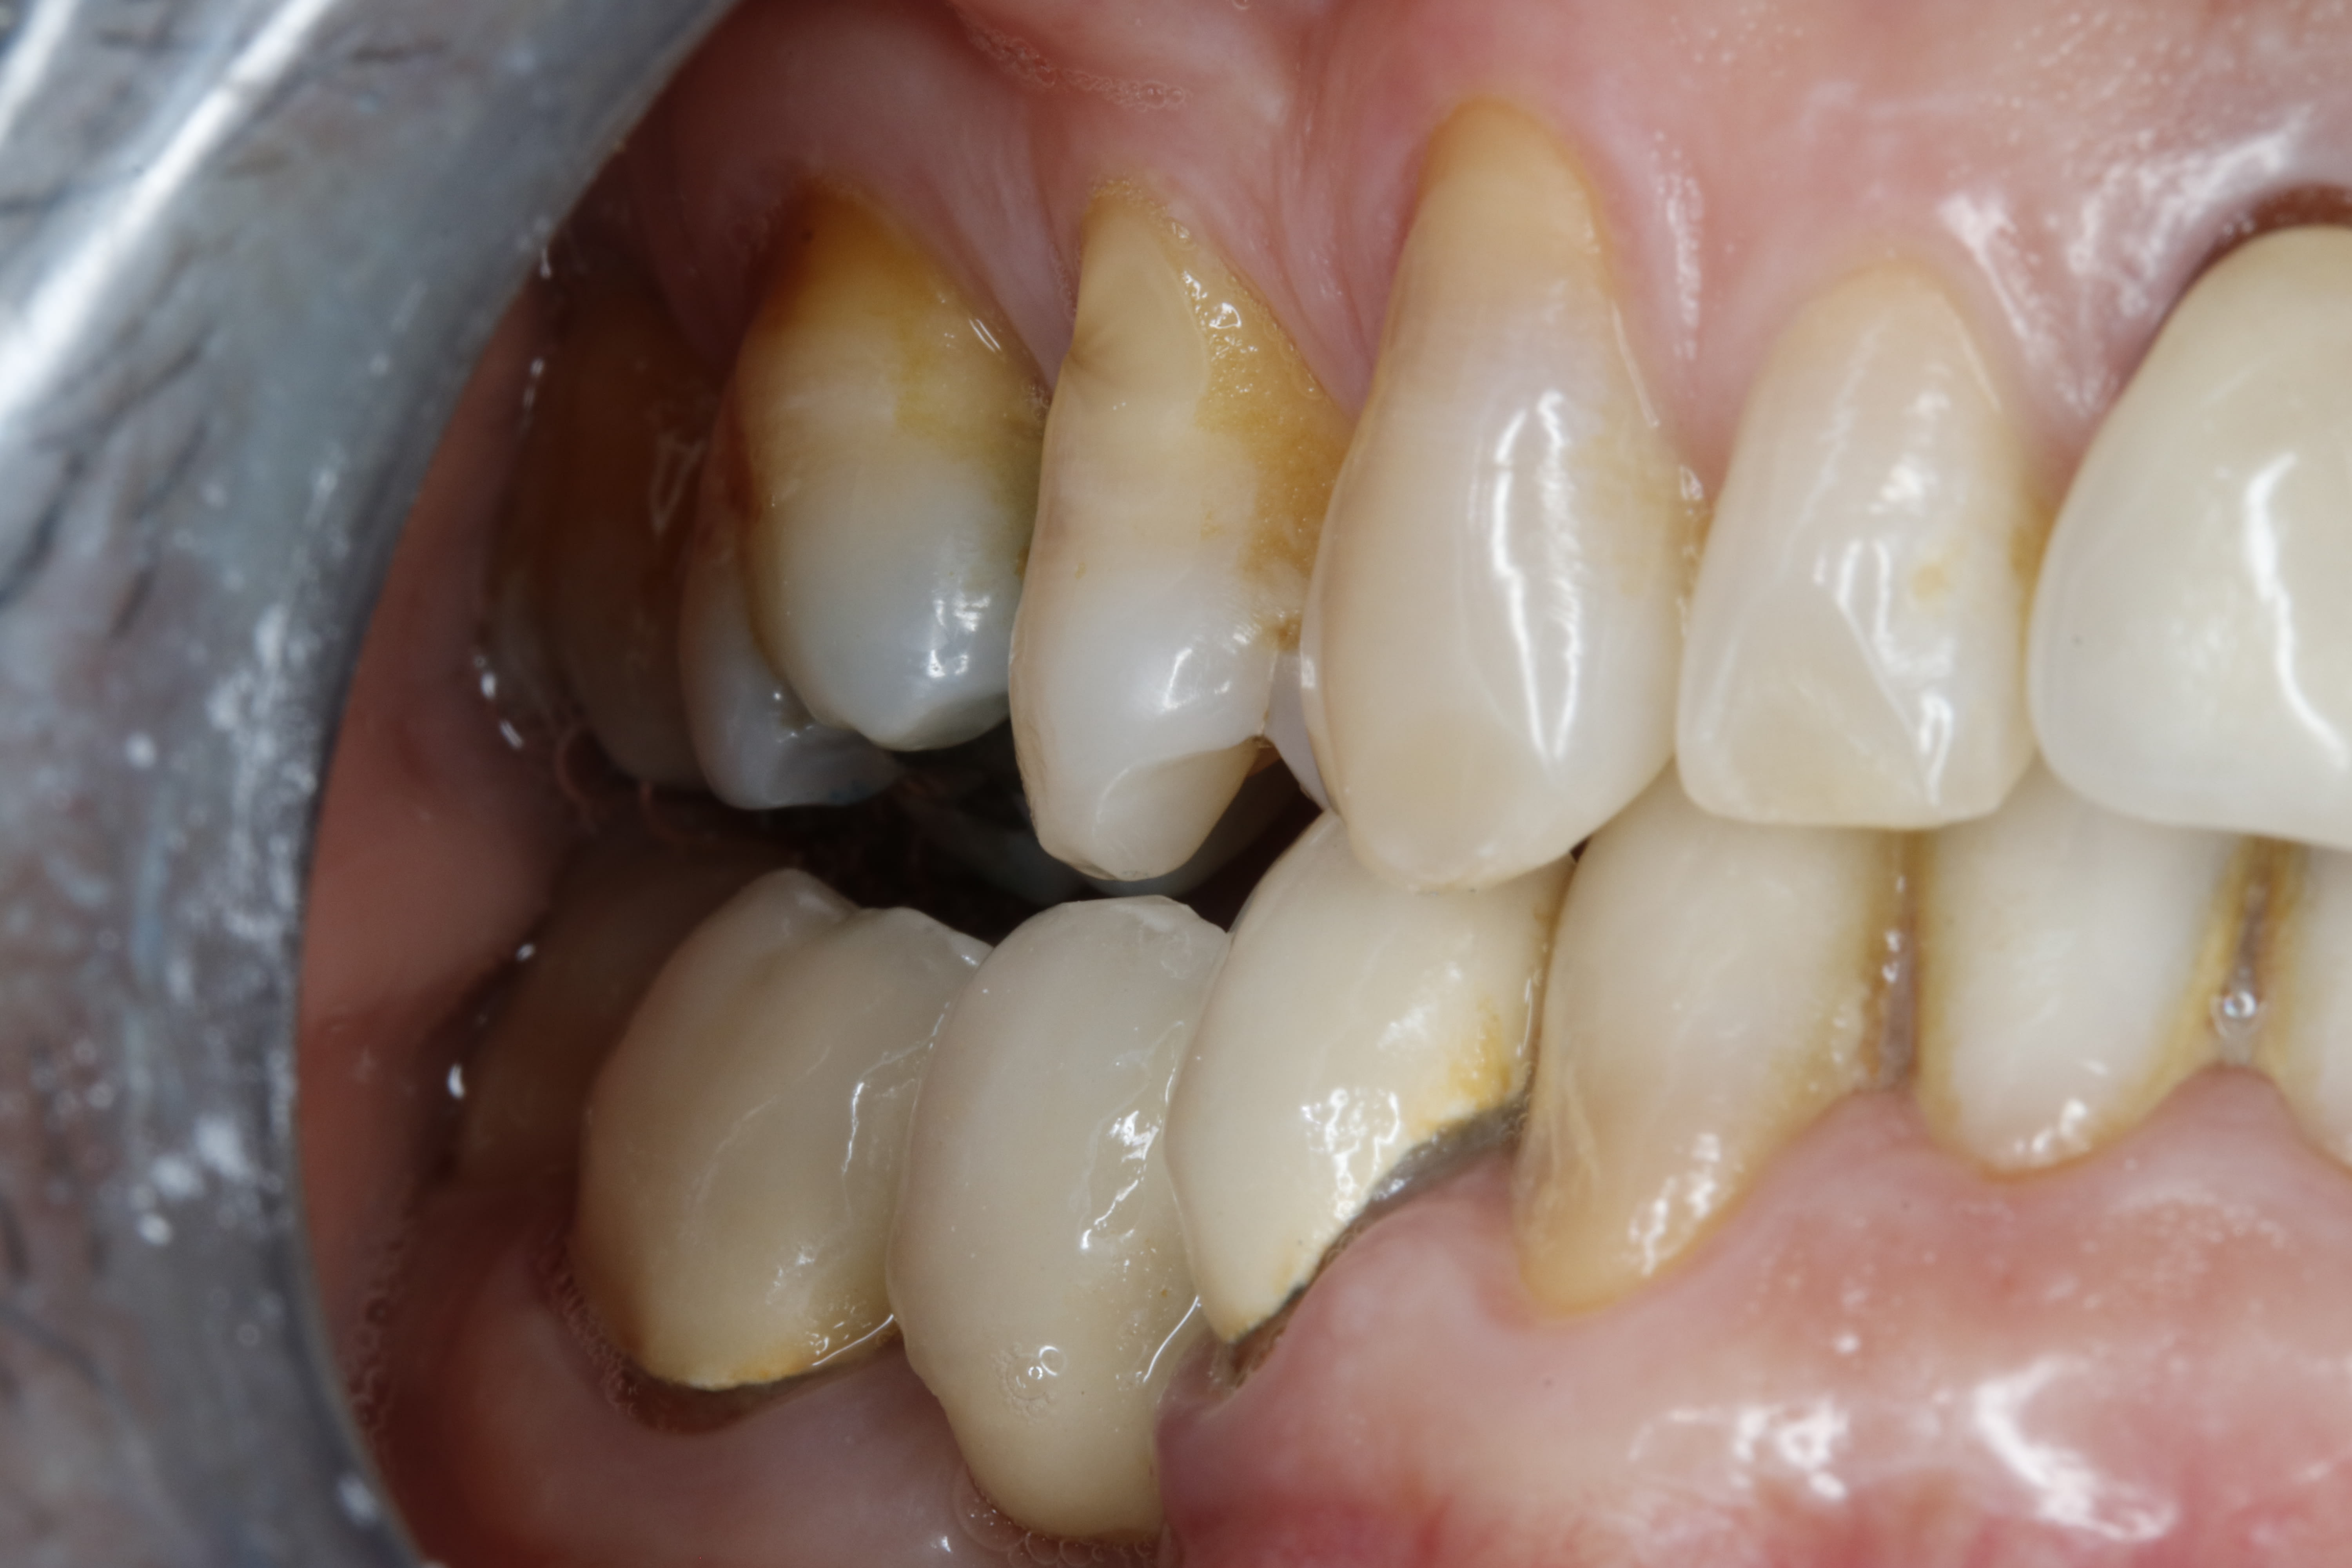

donc voilà le resultat . la chirurgie date de 3 ans .

regardes comme elle est mimi ,la courbe

et il n'y a qu'un seul contact en fermeture ç est sur la centrale .

puis tantôt a gauche ,tantôt à droite il y a 1 et 1 seul contact au fond en fermeture forcée

Il porte une gouttière ou pas (genre gouttière juste en postérieur) ? Comment ça se fait qu'au bout de 3 ans il n'y ait toujours pas de contacts en postérieur ?

En meulant le bloc incisivo-canin inf ça devrait finir par toucher derrière.

Au maxillaire les PM sont en rotation comme si il n'y avait pas eu d'ortho